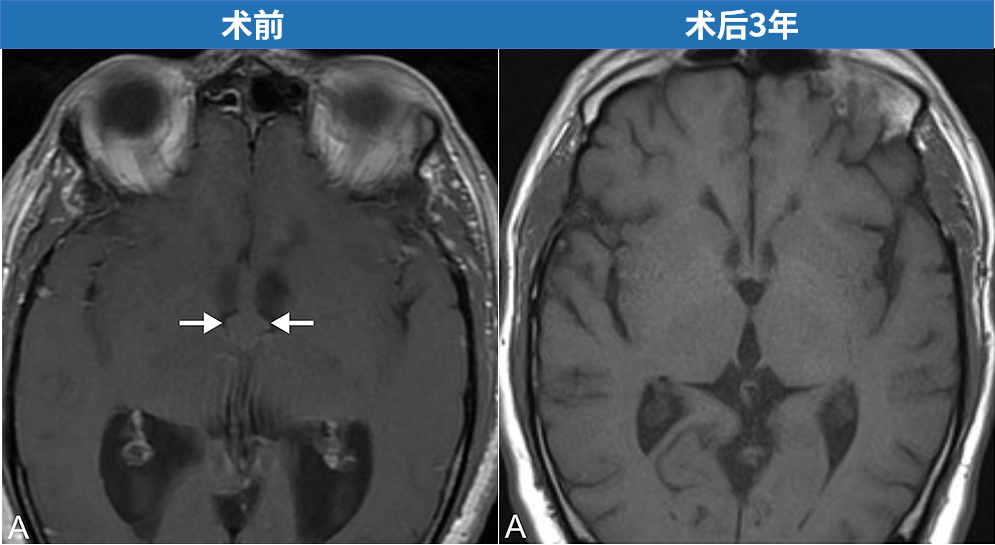

一名55岁男性患者出现了脑积水的相应症状,行走障碍以及记忆力减退等。磁共振成像(MRI)检查发现其第三脑室存在胶样囊肿,并且已出现脑室扩张表现。世界神经外科学会联合会(WFNS)内镜委员会前主席Henry W. S. Schroeder教授对第三脑室胶样囊肿进行内镜下切除,全切后3年无复发。

术前磁共振成像显示胶样囊肿,导致双侧脑室积水。

术后3年获取的 T1 加权(A 为轴位)和 T2 加权(B 为轴位;C 为冠状位;D 为矢状位)磁共振图像显示无囊肿复发。